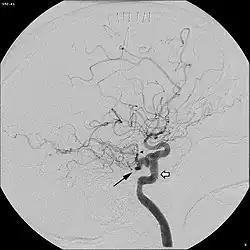

Persistierende Arteria trigemina

Eine bis in das Erwachsenenalter bestehen bleibende Arteria trigemina ist selten. Zum ersten Mal wurde sie 1844 von Richard Quain nach Autopsien beschrieben und angiographisch 1950 zum ersten Mal von David Sutton[5] dargestellt.[2] In Untersuchungen des Kopfes mittels einer Magnetresonanzangiographie wurde sie bei etwa 0,6 bis 0,7 % der Untersuchten gefunden.[6][7] Andere Quellen geben höhere Häufigkeiten von bis zu 2,2 % an, wobei sie sich nicht explizit auf die Magnetresonanzangiographie beziehen.[8] Dabei scheint eine persistierende Arteria trigemina bei Frauen häufiger vorzukommen.[8]